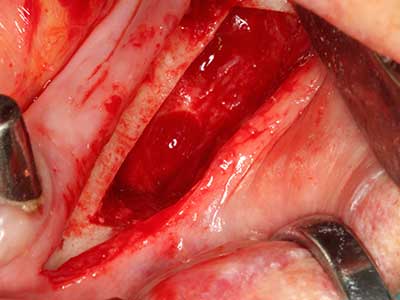

Indication: Bone splitting

Bone tissue is not simply a mineral structure but also contains a substantial proportion of collagen fibres. This means it not only has good compressive strength but also a degree of flexibility, which can be taken advantage of when performing bone augmentations. In the classical expansion procedure using bone splitting, the atrophied alveolar ridge is split longitudinally and carefully expanded after reaching an adequate osteotomy depth (Fig. 13-16), ideally without substantial removal of the periosteum (Brugnami, Caiazzo et al. 2014, Stricker, Fleiner et al. 2014). Screw and plate systems with increasing expansion distance have proven effective in separating the two bone lamellae while remaining below the fracture threshold. In general, residual bone widths of at least 3–4 mm are required (Chiapasco, Zaniboni et al. 2006) to guarantee adequate flexibility and sufficient bone coverage of the future implants. If necessary, a vertical relief osteotomy on one or both sides can improve flexibility. A combination with additional augmentation techniques, particularly on the buccal side, has been described as an alternative to the classical technique.

The splitting procedure is particularly atraumatic and there is no significant loss of dimension when using piezosaws, and there are no significant differences between implants in split jaws and implants in an alveolar ridge without a bone deficit (Chiapasco, Zaniboni et al. 2006, Danza, Guidi et al. 2009). However, sufficient continuous irrigation is essential, particularly with locally restricted and deep splitting to prevent thermal stress in the apical osteotomy regions.